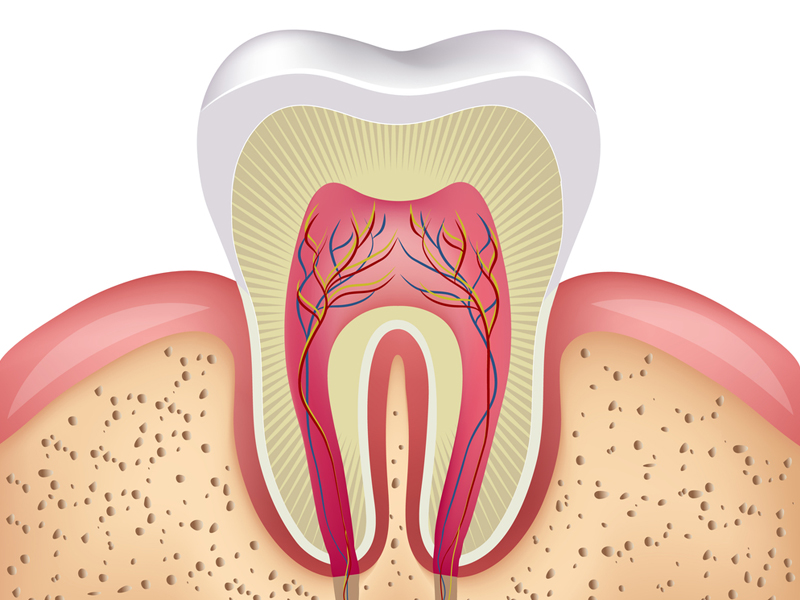

To understand a root canal procedure, it helps to know about the anatomy of the tooth. Inside the tooth, under the white enamel and a hard layer called the dentin, is a soft tissue called the pulp.

The pulp contains blood vessels, nerves and connective tissue, and helps to grow the root of your tooth during development. In a fully developed tooth, the tooth can survive without the pulp because the tooth continues to be nourished by the tissues surrounding it.